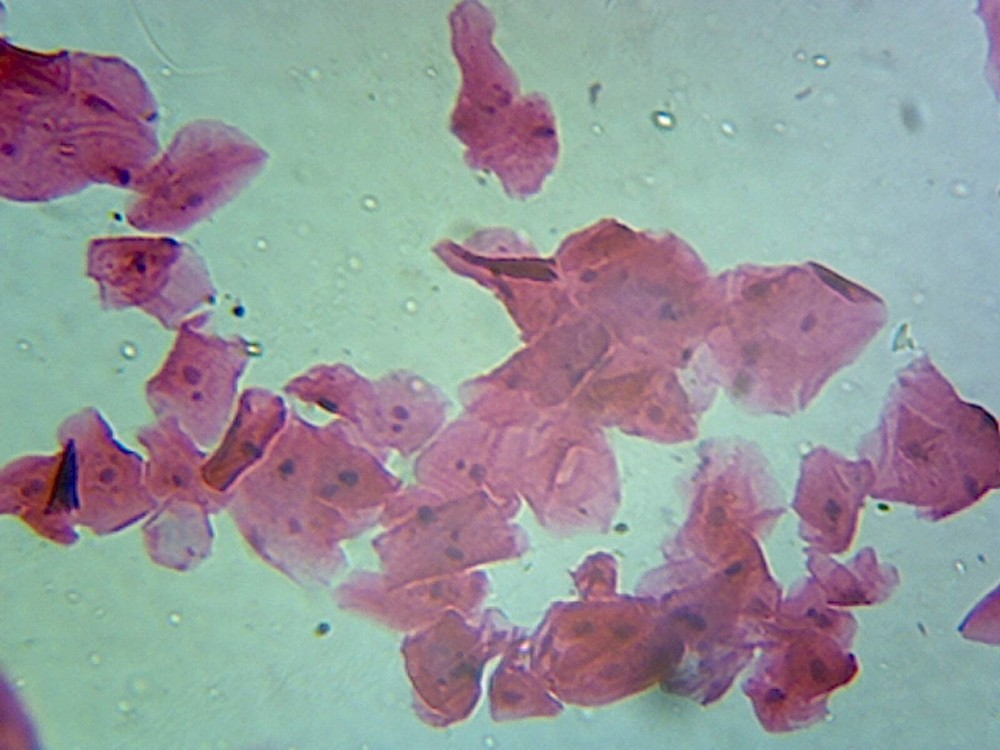

Check the listing for details. Mcmaster Method Microscope Slide - FEC (Fecal Egg Count) or Worm Count, Double C. Color: Blue, Condition: New. Listed at 32.00 USD. FECRT (Fecal Egg Count Reduction Test) Reference Guide Included. Fecal Egg Count Reduction Test (FECRT) Reference Guide Included. Designed for a quick, easy, accurate fecal egg counting process. Make evidenced based deworming protocols by doing your a Fecal Egg Count Reduction Test using the standard, original Mcmaster Egg count slide.